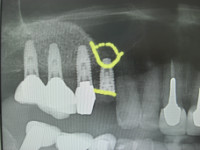

この患者様は右上4番頬側が腫れて痛くて噛み込めないとのことで来院されました。CTにて精査させて頂きましたところ、4番が歯根破折を起こし保存不可能な状態でしたね。

抜歯と同時に埋入できればと考えていたのですが上顎洞底までの骨の厚みが7ミリ程でしたので、抜歯と同時にソケットリフトを施術し洞底を拳上し側方にGBR(骨造成)して予知性のあるインプラント埋入オペとすることにいたしました。